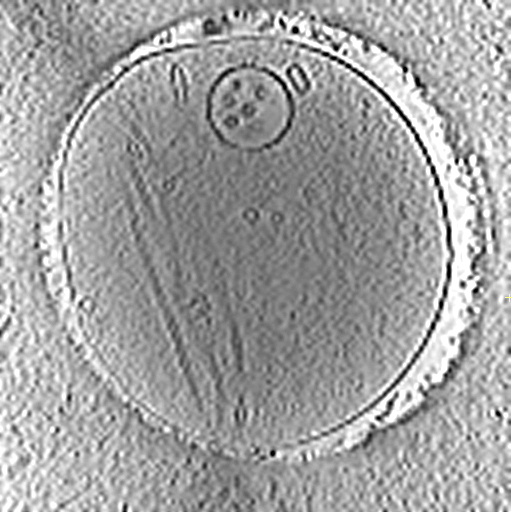

Finally, we experiment on a volume obtained using in a real CryoET acquisition. We use the cryo-electron tomogram of mouse hippocampal neurons [14] (dataset DOI on EMPIAR 10.6019/EMPIAR-10923) display in Fig. 2(a).

We simulate CryoET acquisition (1) by collecting 505050 projections from angles between 7070-70 to 707070 degrees. The measurement SNR, after adding noise to the deformed projections, is 10 dB. Note that this SNR is comparatively more severe for this experiment than in the previous experiments because the volume is much less sparse. The volume density is of size 128×128×9012812890128\times 128\times 90 and the projections are of size 128×128128128128\times 128. The deformations comprise shifts between ±5plus-or-minus5\pm 5 pixels, shear between ±5%plus-or-minuspercent5\pm 5\% and rotation between ±5plus-or-minus5\pm 5 degrees. We run 200020002000 iterations of Adam to solve the optimization problem (6) with λ1=100subscript𝜆1100\lambda_{1}=100, λ2=102subscript𝜆2superscript102\lambda_{2}=10^{-2}, λθ=106subscript𝜆𝜃superscript106\lambda_{\theta}=10^{-6} and λ𝐱=105subscript𝜆𝐱superscript105\lambda_{\mathrm{\mathbf{x}}}=10^{-5}.

We display several slices of the true and the estimated volume in Fig 2(a). The FSC in Fig. 2(b) shows that both the coarse structure and fine details are reconstructed well. We obtain accurate estimates of the deformation as shown in Table 2.

Refer to captionRefer to captionRefer to captionRefer to captionRefer to captionRefer to captionRefer to captionRefer to caption True Est. z=1𝑧1z=1 z=22𝑧22z=22 z=45𝑧45z=45 z=77𝑧77z=77

Fig. 2: a) Reconstruction of CryoET volume [14] (second row) at different depths (z𝑧z), compared with the original volume (first row). b) FSC for the neuron volume of Fig. 2(a) for the proposed approach compared to FBP reconstruction when measurements are perturbed or not by deformations.